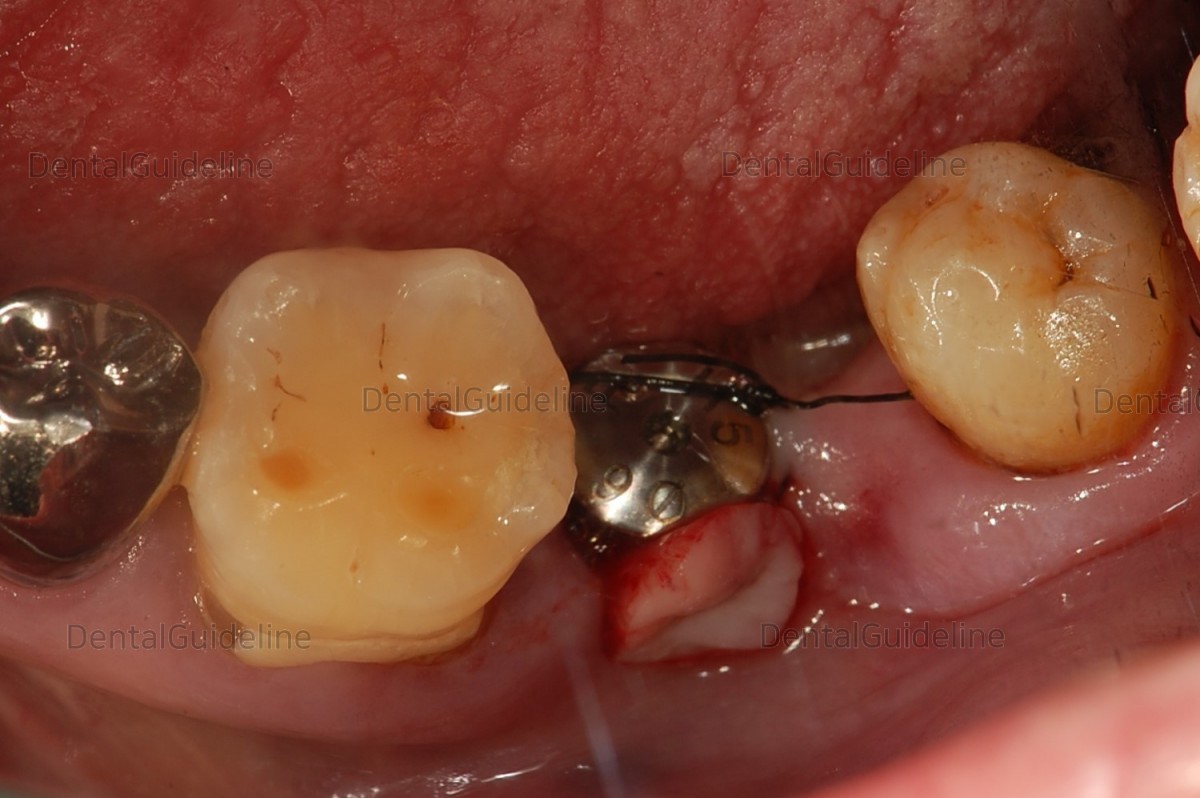

Placement of an implant after soft tissue punching.

The attached gingiva was tied around the healing abutment

It seems to be a rotated gingival graft (= pedicle flap)